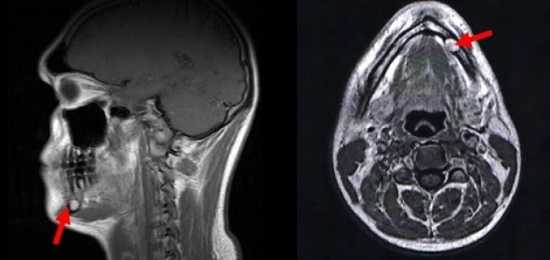

В диагностике новообразований и для оценки состояния кровеносных сосудов челюстно-лицевой системы применяют МРТ с контрастным усилением. В качестве «окрашивающего» вещества используют раствор гадолиния. Препарат заполняет кровеносное русло и межклеточное пространство, визуализируя малейшие изменения сосудистой системы и показывая образования размером от 3 мм.

Как делают МРТ зубов?

Пациенту предлагают лечь на передвижной стол томографа, голову фиксируют при помощи валиков. Во время сканирования следует сохранять первоначальное положение тела, что позволит избежать появления дефектов на послойных изображениях.

Стол с обследуемым перемещается в широкий тоннель, где установлен генератор магнитного поля. Сканирование проводят в трех взаимно перпендикулярных плоскостях, на основании полученных снимков специалист может реконструировать 3D-модель ротовой полости и височно-нижнечелюстного сустава.

При использовании контрастного усиления сначала делают серию нативных снимков. Затем исследование приостанавливают, пациенту с помощью катетера, соединенного с автоматическим инъектором, вводят раствор гадолиния и продолжают сканирование.

Сеанс МРТ занимает от 15 до 20 минут. При использовании контраста процедура длится около получаса.

Расшифровка фото снимков МРТ зубов

Послойные фотографии позволяют оценить состояние рыхлых структур ротовой полости, челюстно-лицевой зоны, ВНЧС. Снимки МРТ не дают визуализации строения твердых тканей зуба. По результатам сканирования врач описывает:

МРТ головы в сагиттальной и аксиальной проекциях, стрелка указывает на образование в области нижней челюсти